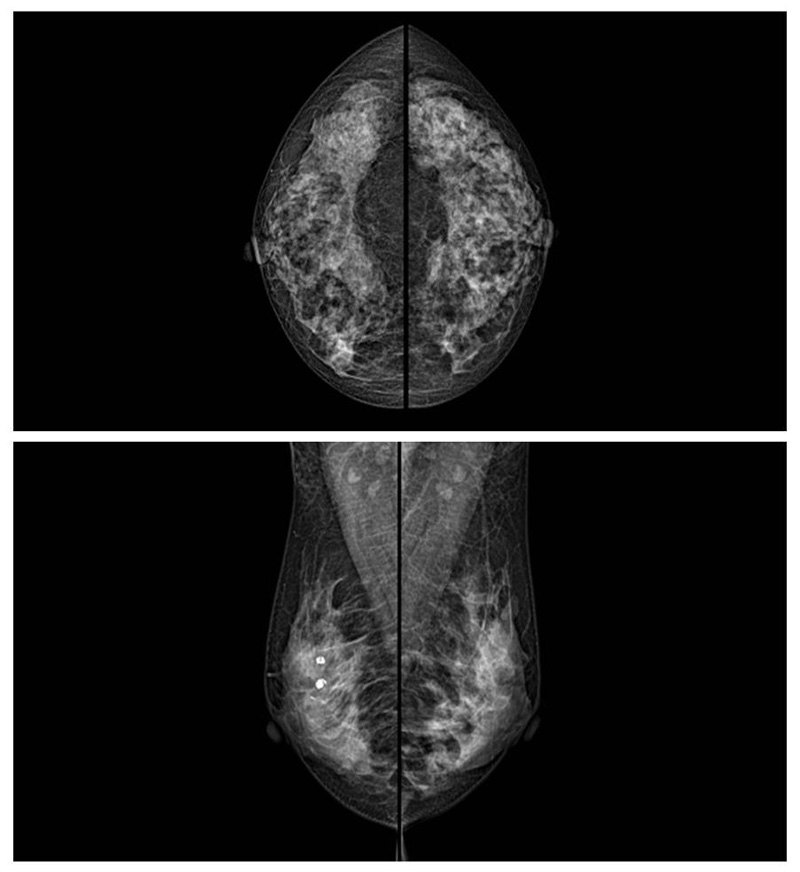

乳腺癌的发生率越来越高,已经是91抖音视频在线观看国家的癌症之一已成为女性健康“头号杀手”。乳腺DR可提高乳腺癌早期检出率并精准定位。发现和诊断早期乳腺癌最有效的方法之一,明显利大于弊女性都要重视乳腺的检查。辐射很小最简便、最可靠、无创性检查手段,做一次乳腺DR的剂量相当于7周的正常生活。尤其是对于40岁以上的女性尤为重要,那么乳腺DR是怎么进行检查的呢?91抖音视频在线观看来了解一下,为广大朋友在检查前有点心理准备。检查时候是避开经期的前后,月经来后的7天左右比较合适。需要脱衣服检查,根据拍片的摆位要求,有头尾位置,内外斜位,还有侧位。定点放大压迫方法可以更细微清晰的检查出病灶。